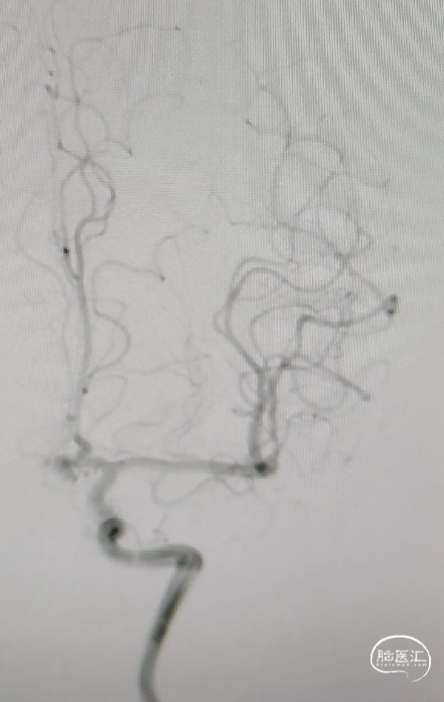

➢术后造影

术后造影显示各分支血管血流通畅。

双融积成像显示支架打开贴壁良好,瘤体少量残留。